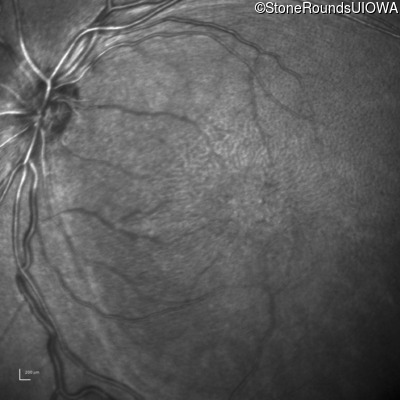

Infrared Fundus Photograph - Left - 10/40

Exemplar